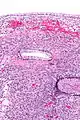

| Micrograph showing a mucinous cystadenoma of the ovary. H&E stain. | |

Mucinous cystadenoma is a benign cystic tumor lined by a mucinous epithelium.